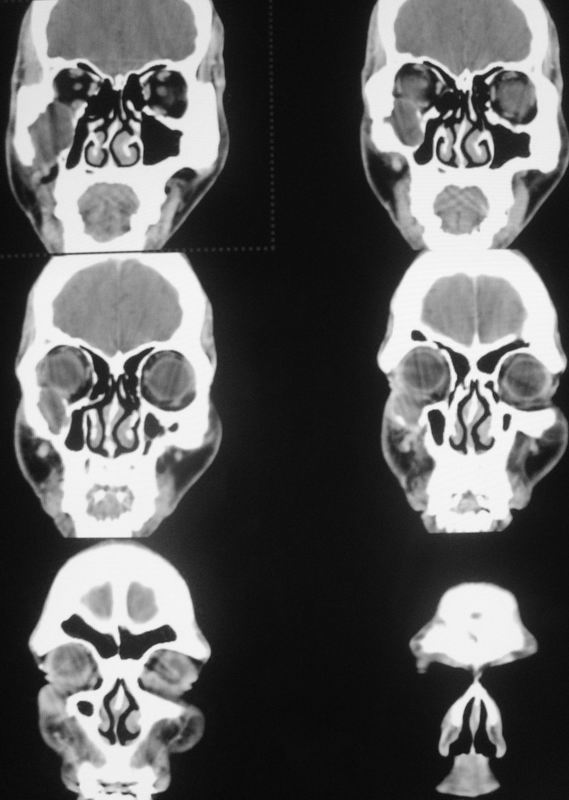

以下是引用zsl6918在2008-5-6 14:41:00的发言:[br]右侧颞下窝内囊性占位(增强未见强化),同侧上颌窦受压变形移位,提示慢性过程。右侧上颌骨局限性吸收破坏,提示良性病变。

以下是引用长城干红在2008-5-6 15:05:00的发言:[br]考虑:右侧颞下窝神经源性良性肿瘤。

以下是引用xuhuihong在2008-5-6 14:57:00的发言:[br]右侧颞下窝内囊性占位(增强未见强化),同侧上颌窦受压变形移位骨质吸收变薄,提示慢性过程。右侧上颌骨局限性吸收破坏,提示良性病变。考虑神经源性肿瘤可能,期待结果。